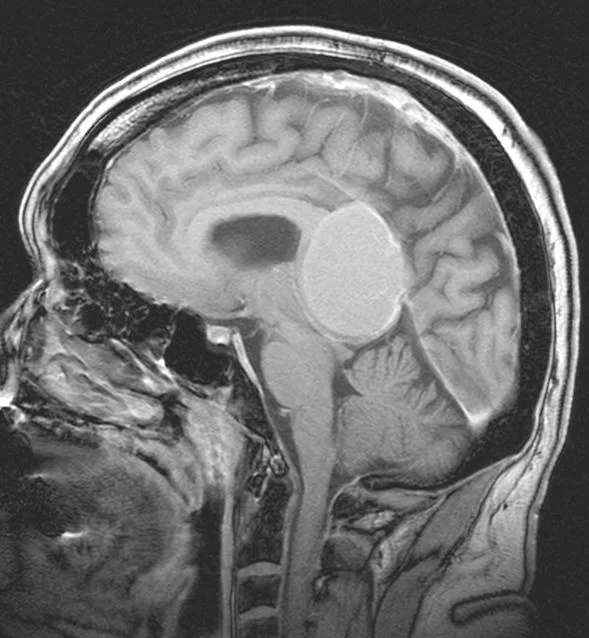

Αραχνοειδής Κύστη Εγκεφάλου

Ασθενής γυναίκα 58 ετών με πονοκεφάλους και διαταραχές όρασης. Ο οφθαλμολογικός έλεγχος έδειξε οίδημα οπτικών θηλών άμφω και σημαντικό περιορισμό των οπτικών πεδίων. Τα συμπτώματα

Περισσότερα